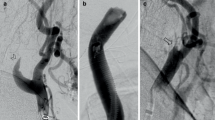

Of 4 patients with CHS, case 1 experienced headache 4 h after CAS, with a 59.2% quantitative increase in CBF, case 2 had eye pain and deterioration of consciousness 2 h after CAS, with a 53.7% increase in CBF, case 3 had deterioration of consciousness with restlessness 1 day after CAS, with a 79.7% increase in CBF, and case 4 experienced headache and CT showed intracerebral hemorrhage 2 days after CAS, with a 73.0% increase in CBF, as shown in Fig. 3.

Angiogram in a 61-year-old man with severe left extracranial carotid artery stenosis with asymptomatic stenosis (83%) (A). A post-CAS angiogram showed that stenosis improved (B). Preoperative 123I-IMP SPECT at rest (C) and post-acetazolamide challenge (D) indicated a resting CBF of 23.77 mL/100 g/min and CVR of 6.6% in the middle cerebral artery territory, as measured by the SEE-JET program. 123I-IMP SPECT immediately (E), 3 days (F), and 7 days (G) after CAS showed ipsilateral increases in quantitative CBF of 41.12, 38.99, and 34.40 mL/min/100 g, respectively, again measured with the SEE-JET program. CT on postoperative day 2 showed intracranial hemorrhage on the ipsilateral side (H)